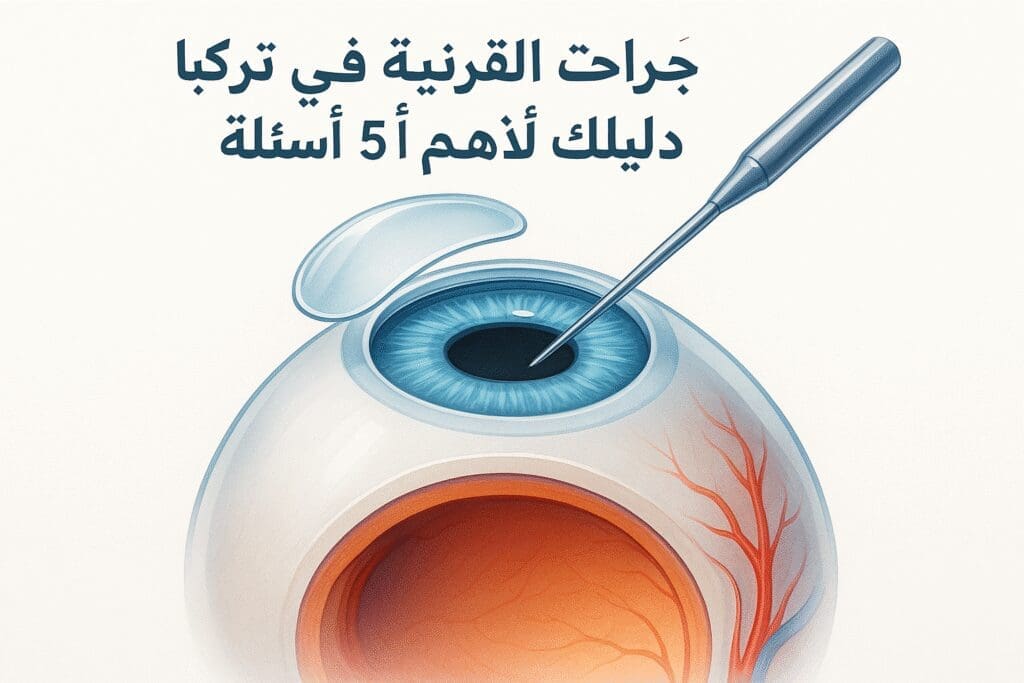

أطباء العينية

74 listings

مقالات طبية من مساهمات الأطباء